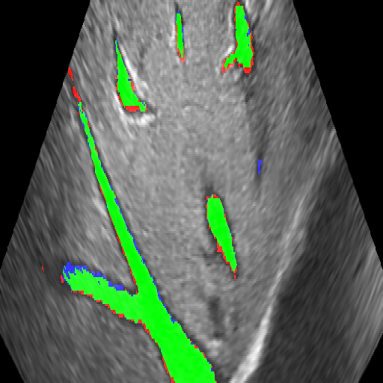

[5pt]Refer to caption(a) Dice = 0.719 \stackunder[5pt]Refer to caption(b) Dice = 0.640 \stackunder[5pt]Refer to caption(c) Dice = 0.861

Figure 1: Examples of test set segmentation results, true positives are colored green, false positives blue and false negatives red

The reduced filter U-Net obtained Dice scores of 0.740 (±0.02plus-or-minus0.02\pm 0.02) and 0.781 (±0.07plus-or-minus0.07\pm 0.07) for the 3D acquired and 2D stacked US images respectively compared to an inter-observer variability of 0.879 (±0.02plus-or-minus0.02\pm 0.02) (table LABEL:tab:Dice). IoU is reported at 0.584 (±0.02plus-or-minus0.02\pm 0.02), 0.645 (±0.09plus-or-minus0.09\pm 0.09) and 0.785 (±0.03plus-or-minus0.03\pm 0.03) respectively. Figure 1 shows segmentation results for several selected cases.

This study shows that it is possible to accurately segment hepatic vessels on US imaging with a relatively small dataset, but deviates from the inter-observer performance. Furthermore, our results seem favorable [Milko et al.(2008)Milko, Samset, and Kadir, Wei et al.(2019)Wei, Xu, Alpers, Tianbao, Wang, Rak, and Hansen], but also slightly underperform [Mishra et al.(2018)Mishra, Chaudhury, Sarkar, Manohar, and Soin] when compared to 2D segmentation literature. Overall under-segmentation of the inferior vena cava is observed, especially near the edges of the volume (figure 1b). We suspect that this is caused by incomplete vessel information (i.e. incomplete visibility of vessel cross section), strongly influencing the Dice due to its large volume. Comparing the proposed network to a network with the original amount of filters was not possible due to GPU memory limitations. The learned features between the different acquisition methods appear exchangeable as there appears no difference in segmentation performance. Whilst promising results have been demonstrated, further validation will be done by expanding the data set. In the future we will expand this methodology by discriminating between different types of vasculature (i.e. hepatic and portal vein) as well as parenchyma. Moreover, we will explore the use of these segmentations for automatic registration with a MRI model in a navigation surgery setting. These segmentations are expectantly sufficient to realize a centerline-based registration pipeline in the future.